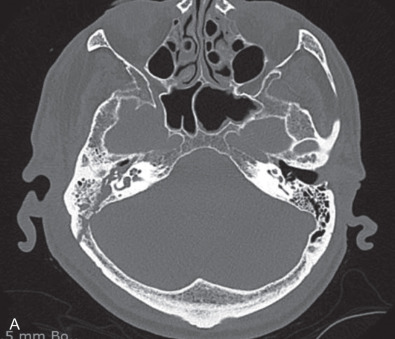

Computed tomography (CT) is the best modality for assessing temporal bone fractures ( Fig. 1.17.2 ). Opacification of air cells and pneumocephalus can suggest a fracture. Pneumolabyrinth suggests OC involvement and is found in up to 8% of fractures. A head, maxillofacial, or cervical CT can detect a fracture without the need for a dedicated temporal bone scan. The sensitivity and specificity of a maxillofacial CT scan in cases of blunt head trauma and associated vascular injury are greater than 90% and imply a negative predictive value of >95%. A separate HRCT can add cost, radiation exposure, and time to a work-up without significantly changing management. However, if standard imaging does not show a fracture but physical exam suggests its presence, or if management dictates the superior anatomical information offered by HRCT, then a dedicated temporal bone CT should be obtained. In cases where surgical management is considered or an unreliable clinical exam is present, a HRCT scan provides adjuvant information that changes treatment.

HRCT should include proper filters for bone edge detection and reconstructions from small fields of view with minimal slice thickness (e.g. 0.5 mm) and spacing (ideally 0 mm). Scans obtained with spiral technique or from multidetector scanners using 0.5 mm 3 or smaller voxels allow for reconstructions in any plane without loss of resolution. For pediatric patients, low-dose radiation protocols may be used; however, evaluation of small structures may be difficult. The evolution of flat panel CT is a promising development that may offer even higher resolution of bony anatomic detail with lower total radiation dose. No matter the technique used for HRCT, the clinician should review the images and correlate physical findings with imaging ( Box 1.17.1 ).